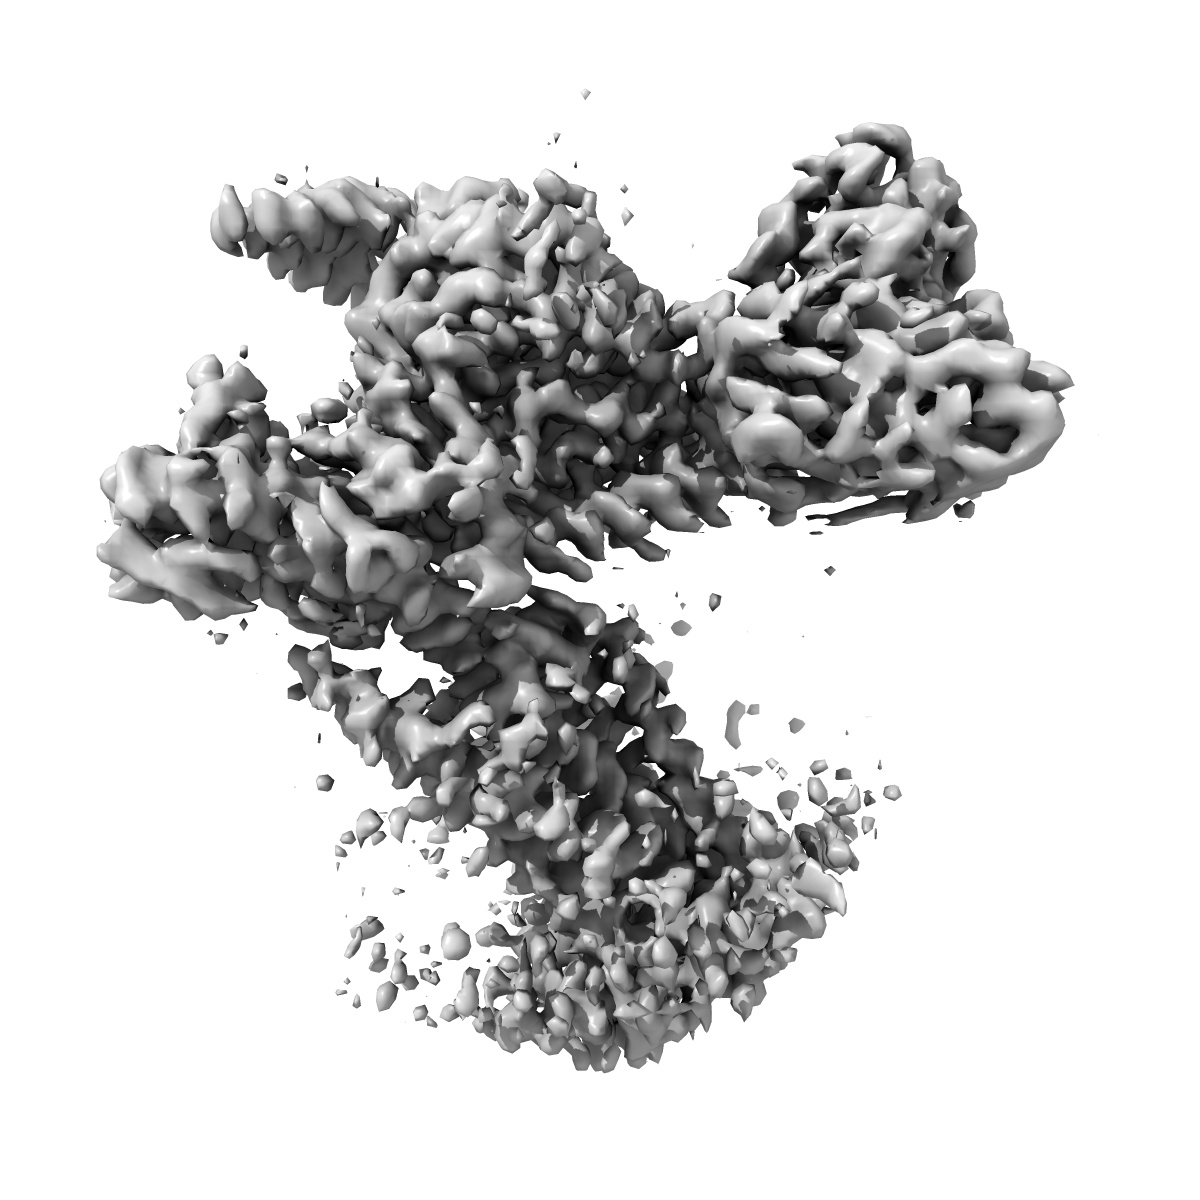

Cryo-EM Structure of the Prostaglandin E Receptor EP4 Coupled to G Protein

Single-particle3.5 Å

Sample: Cryo-EM Structure of Prostaglandin E Receptor EP4 Coupled to G Protein

Single hormone or synthetic agonist induces G s /G i coupling selectivity of EP receptors via distinct binding modes and propagating paths.